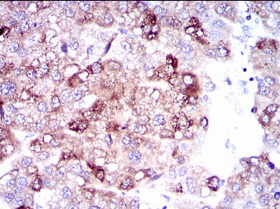

SLC27A5 Mouse Monoclonal antibody[4B19]

IHC    1/200 - 1/1000